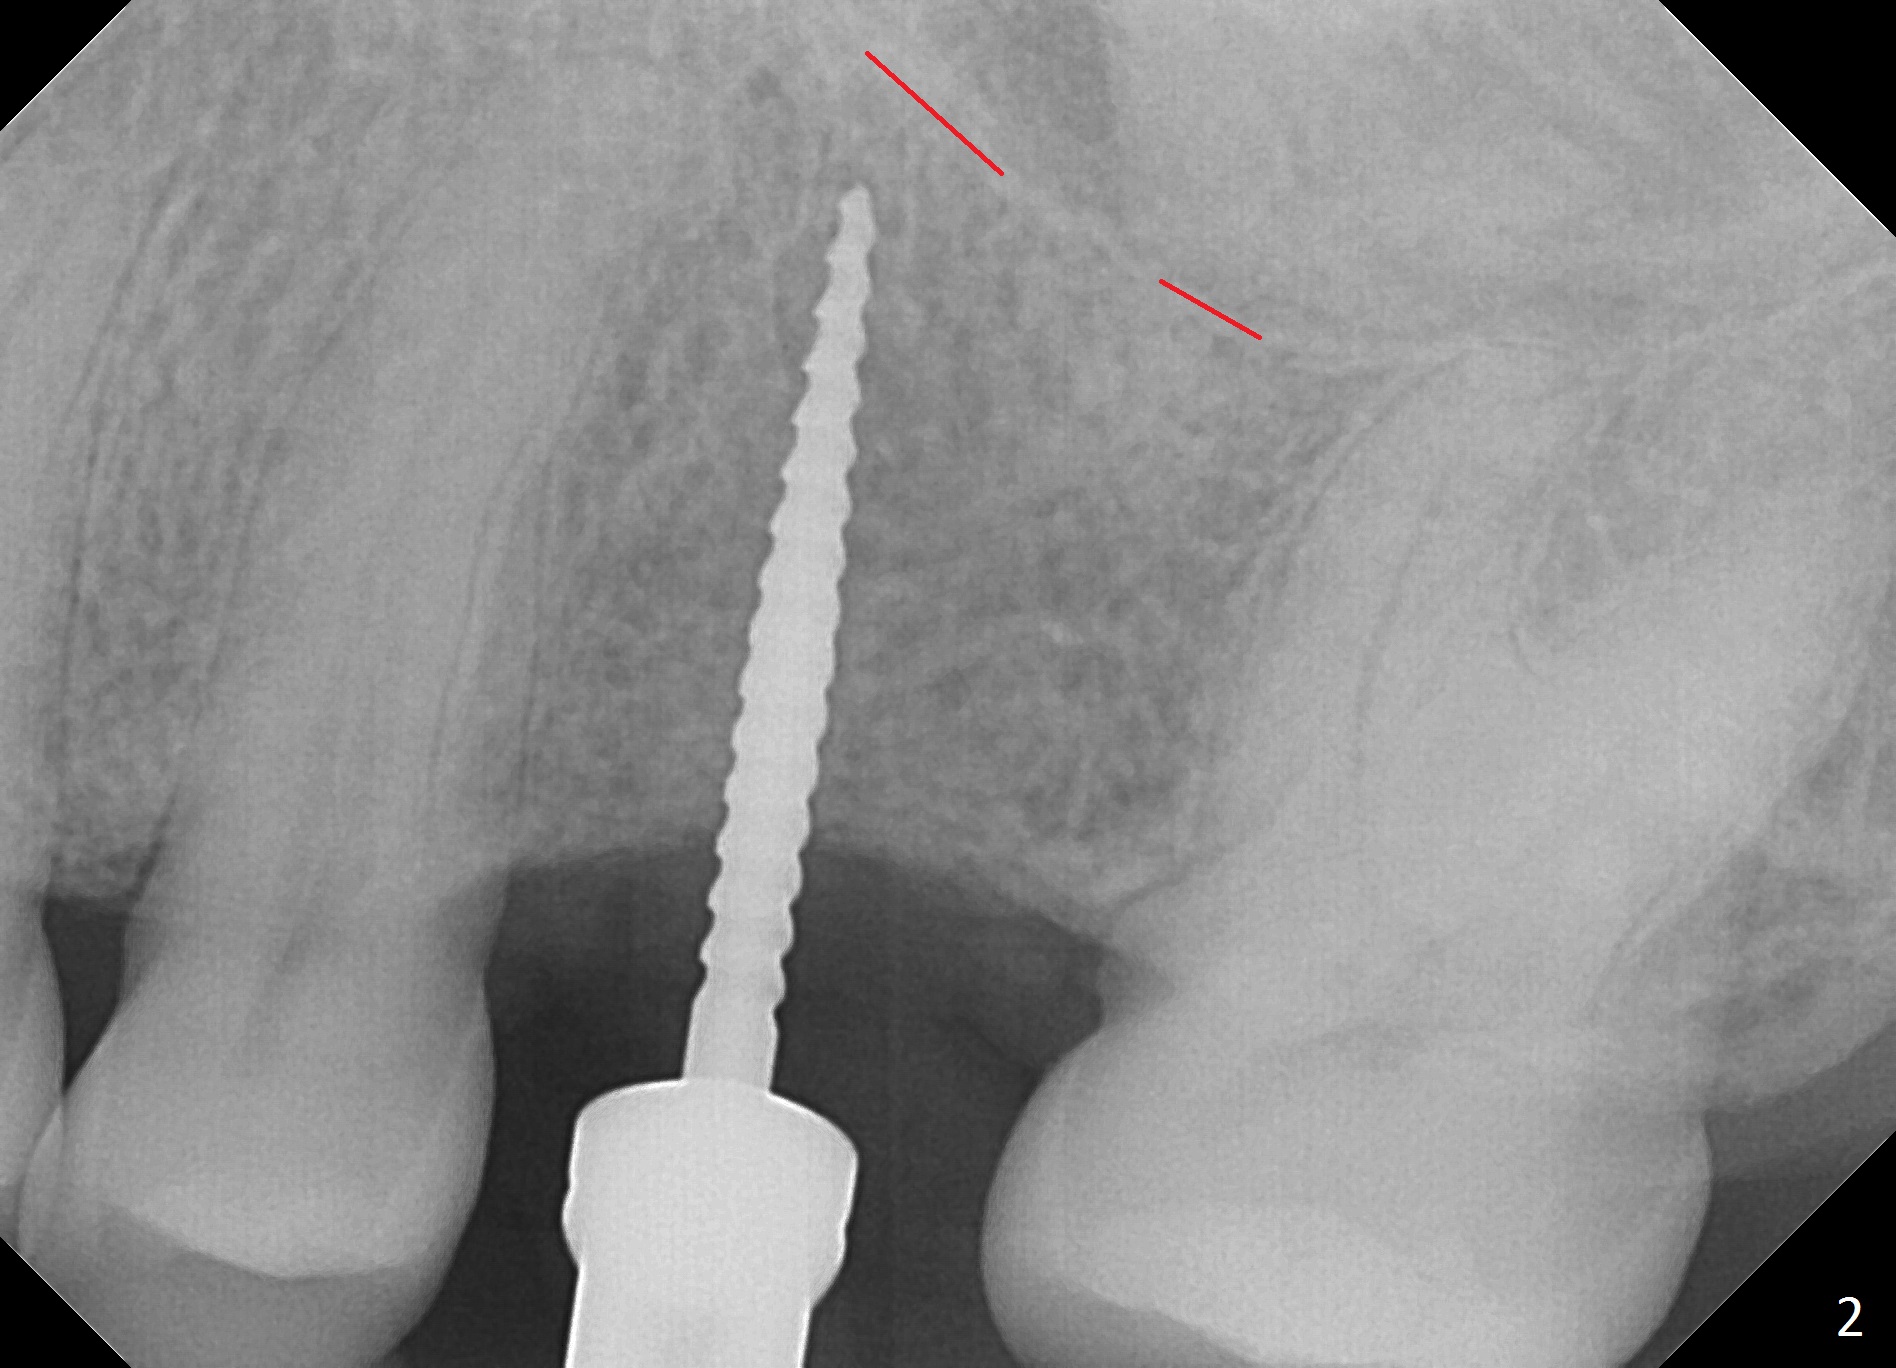

The edentulous area at #14 is moderately atrophic, After incision, the bone is too hard for #15 blade for bone expansion. Osteotomy is initiated with 1.2 mm drill, followed by insertion 1.3/2.3 mm bone expander (Fig.1). Use the same instruments are reused twice to change the trajectory (Fig.2,3). Finally Lindamann bur is utilized to move the osteotomy distally by ~ 2 mm; bone expansion continues until 2.4/3.7 mm expander for 13 mm with 50 Ncm (Fig.4). The last expander 3/4.4 mm barely enters the osteotomy for 6 mm. A 3.7 mm drill has to be used for 12 mm before placement of a 4.5x11.5 mm implant with >35 Ncm (Fig.5). A 5.5x5(3) mm abutment is placed with allograft (<) placed around the implant. Following suturing, periodontal dressing is applied around the implant. The abutment dislodges 3 months postop (Fig.6). Crown is delivered 3 weeks later. The abutment screw is retightened ~ 2 months later. He is a bruxer. The abutment screw is loose again <2 years post cementation (6 months post #18 screw retightenting and occlusal reduction), probably related to distal implant placement (Fig.7).